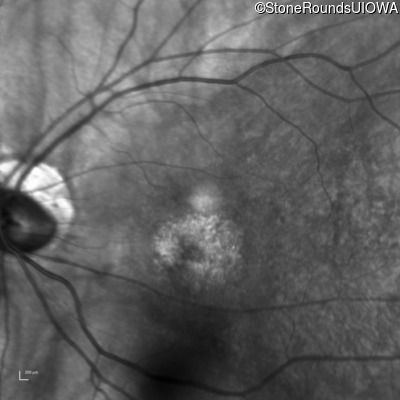

XL Cone and Cone Rod Dystrophy (IA1bi)

XL Cone and Cone Rod Dystrophy (IA1bi)

This 52 year old man had normal vision until his mid 30's when he began to have trouble distinguishing colors. the issuing 10 years he had a gradual loss of visual acuity accompanied by increasing photophobia.

| XL Cone and Cone Rod Dystrophy | RPGR | Gly1093 del2gGA | XL |